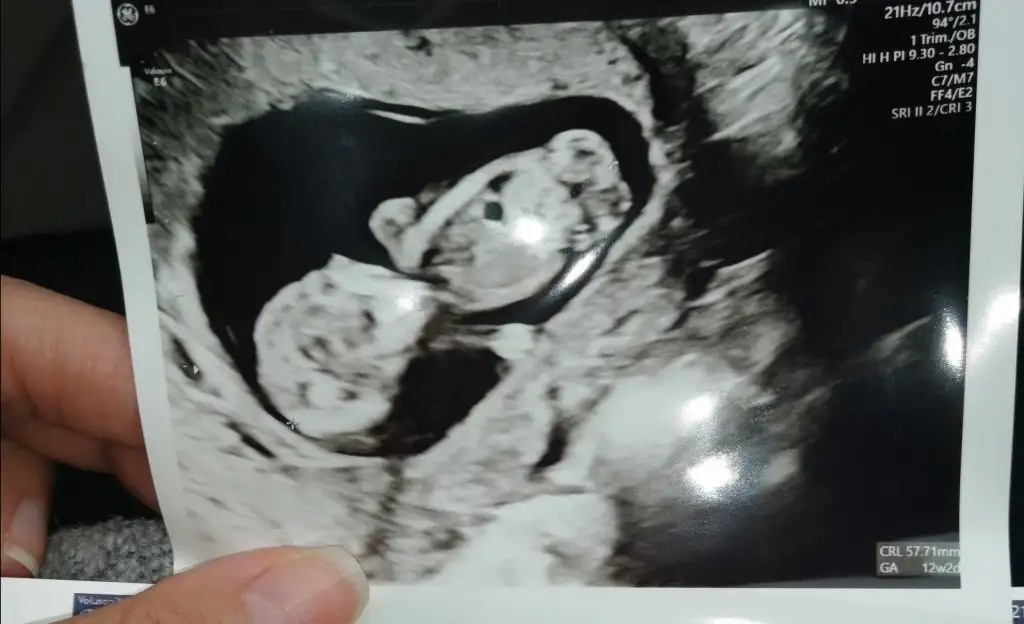

Ay maşallah bebiş poposunu dönmüş benimkide hep böyleGünaydın canımYok canım ya malesef hafif hafif var yine ...Bu arada ben de şimdi doktordan çıktım çok şükür iyi bı daha 12. Haftada ikili için cagirdi...

Normalde bugün 10+1 .... Ultrason da 10+6 çıktıBiraz önden gidiyo galiba

Hadi ya poposu mu dönük bende anlamaya çalışıyodumAy maşallah bebiş poposunu dönmüş benimkide hep böyleiyi bakmışsın annesi

Evet evet poposu dönükHadi ya poposu mu dönük bende anlamaya çalışıyodumAyy çok güldüm ya doktora sordum dediki tüp bebek de olabiliyo böyle bı kac gün dedi ama bakalım Annemle konuştum oda diyoki çabuk gelisiyosa kesin kızdır